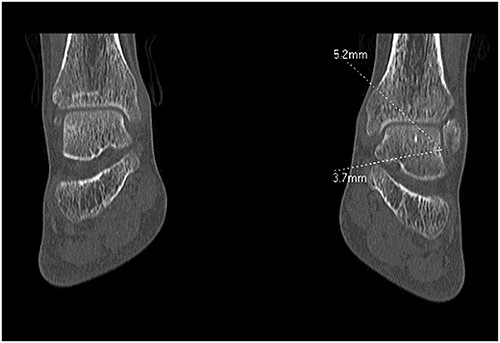

A 28-year-old male patient presented with a history of ankle pain and difficulty with weight-bearing activities on the right side. Radiographic evaluation revealed a large osteochondral defect in the talus. (Figs 1–3).